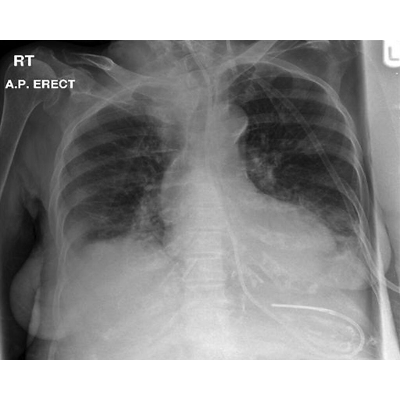

This is a research article that articultes the importance of checking the nasogastric tube placement. It states that most nasogastric tube complications or misplacements can be preventable by performing a chest x-ray.